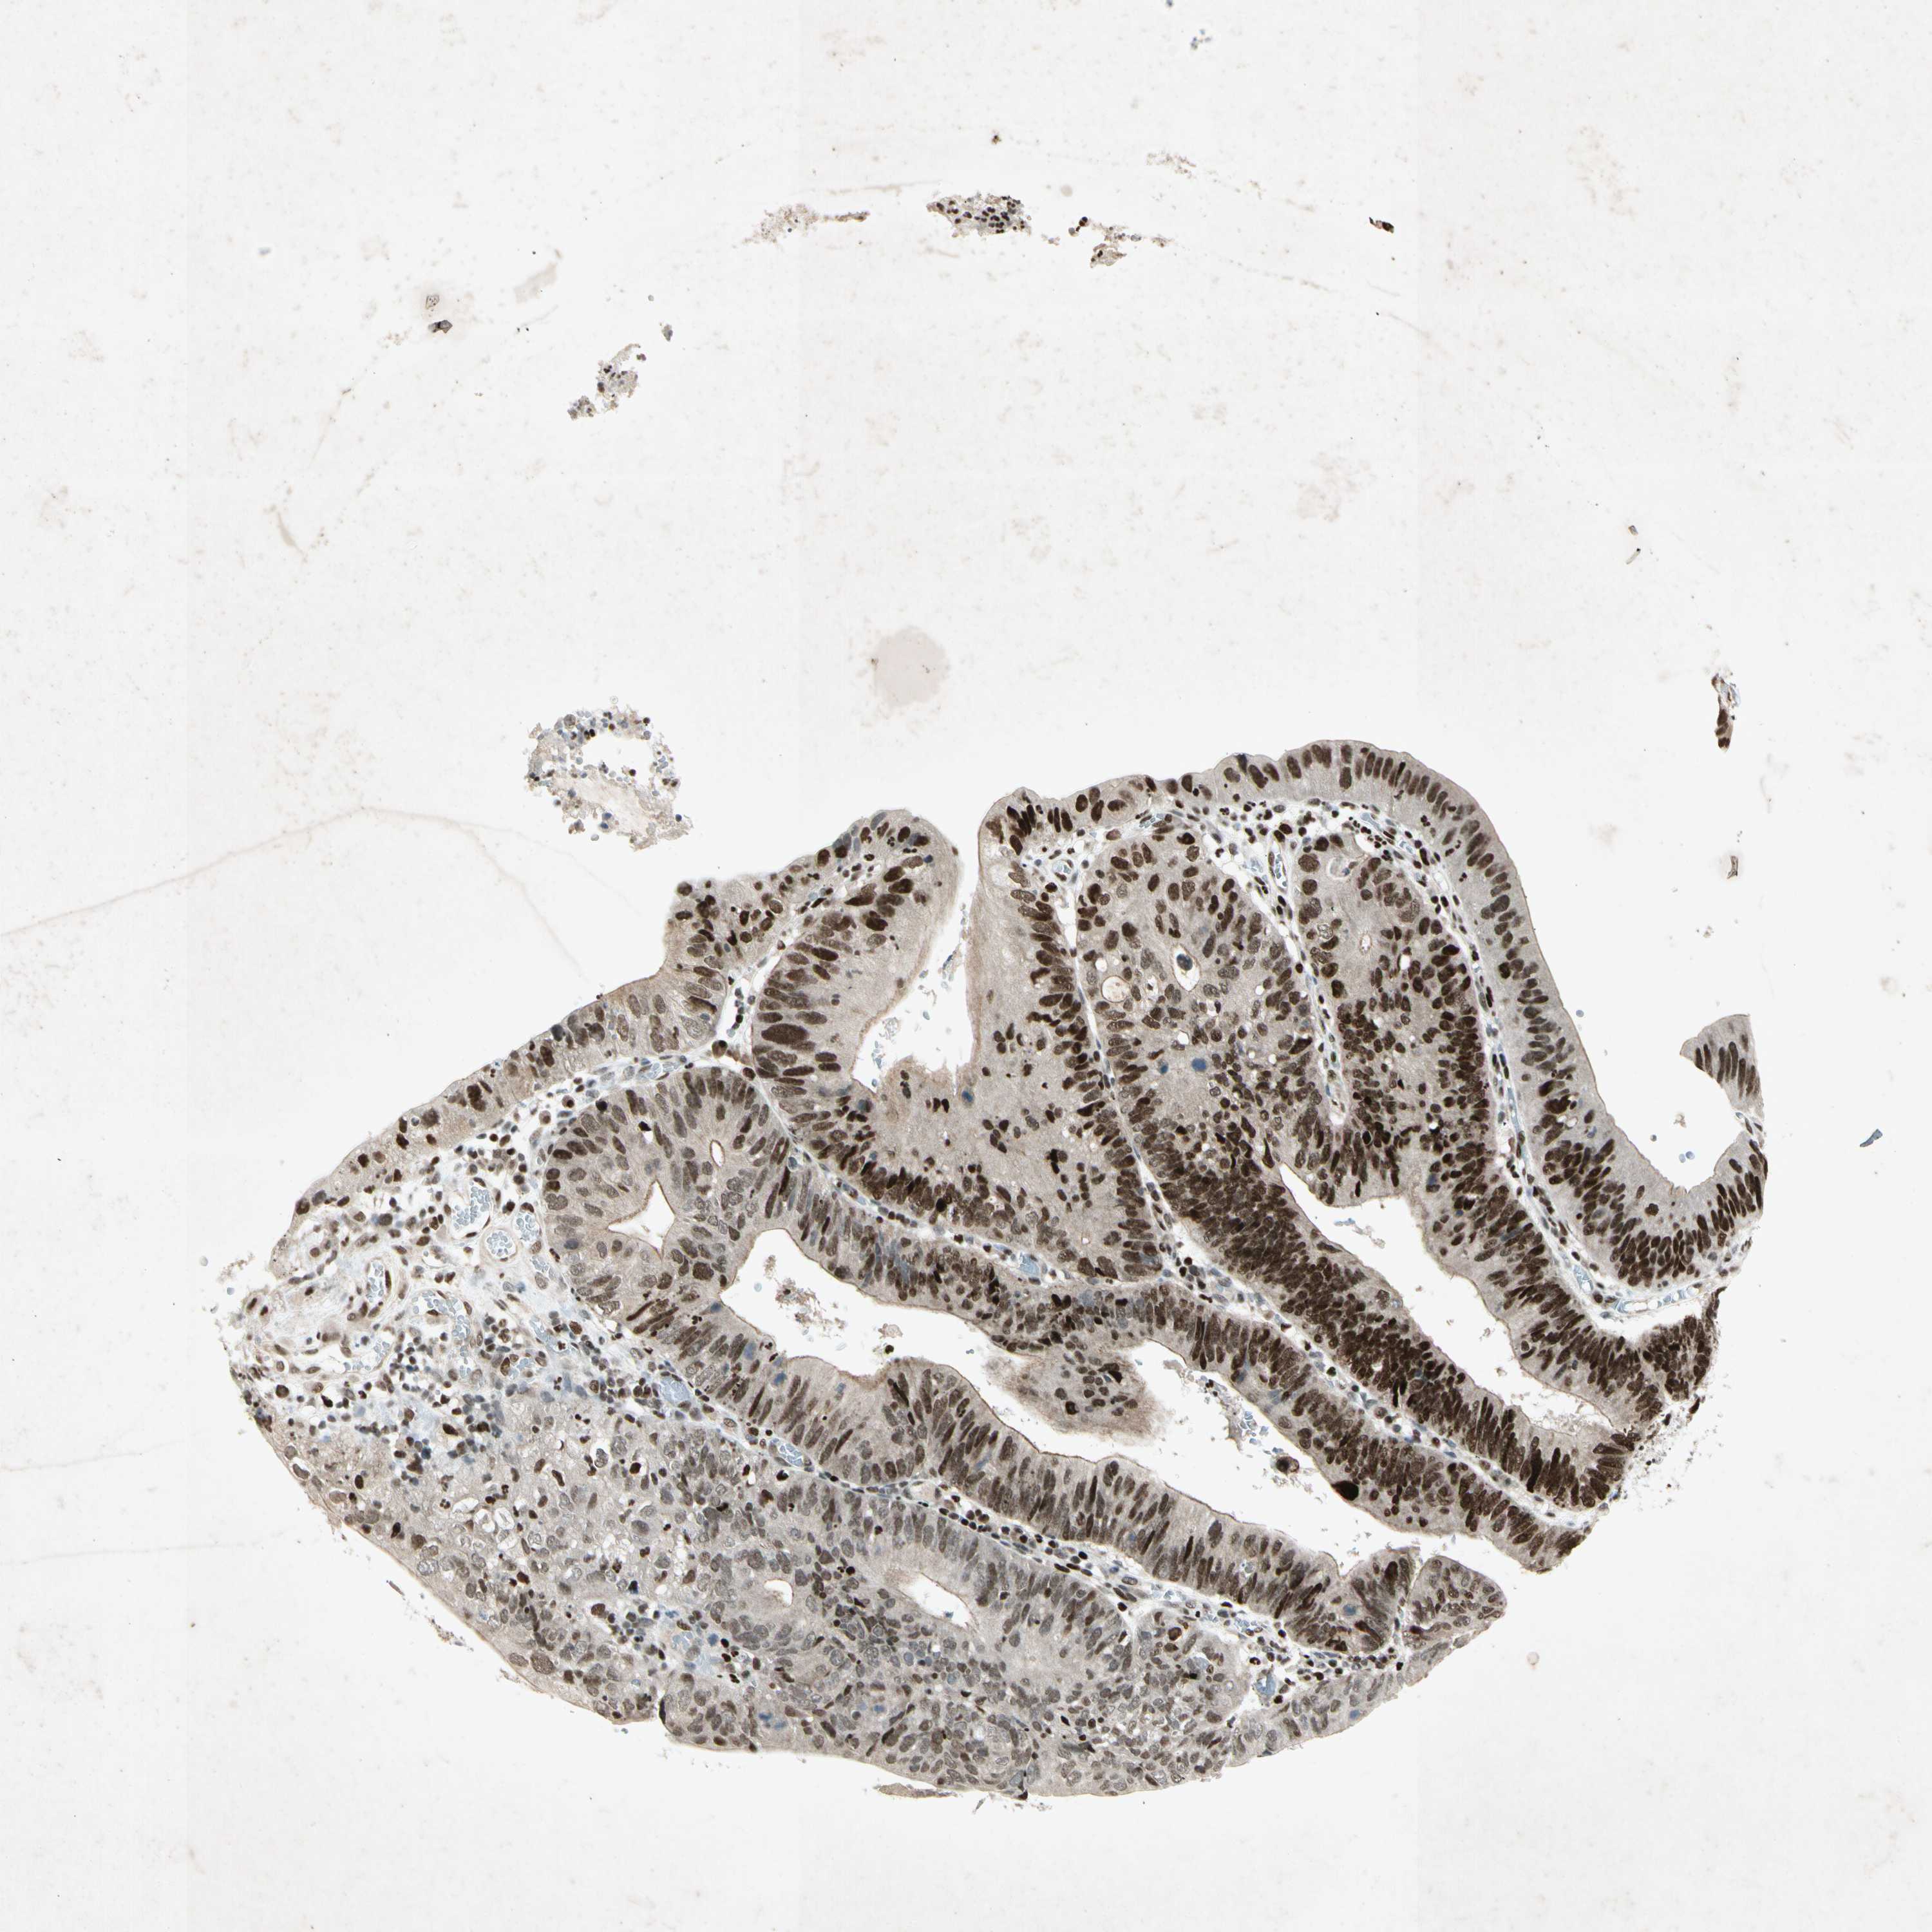

STOMACH CANCER - Protein expressioni

A mouse-over function shows sample information and annotation data. Click on an image to view it in a full screen mode. Samples can be filtered based on level of antibody staining by selecting one or several of the following categories: high, medium, low and not detected. The assay and annotation is described here.

Note that samples used for immunohistochemistry by the Human Protein Atlas do not correspond to samples in the TCGA dataset.

Antibody stainingi

Antibody staining in the annotated cell types in the current human tissue is reported as not detected, low, medium, or high, based on conventional immunohistochemistry profiling in selected tissues. This score is based on the combination of the staining intensity and fraction of stained cells.

Each image is clickable and will lead to virtual microscopy that enables deeper exploration of all samples and also displays staining intensity scores, fraction scores and subcellular localization as well as patient and tissue information for each sample.

Antibody HPA008079

Staining

High

Medium

Low

Not detected

Intensity

Strong

Moderate

Weak

Negative

Quantity

>75%

75%-25%

<25%

None

Location

Nuclear

Cytoplasmic/membranous

Cytoplasmic/membranous,nuclear

Adenocarcinoma, NOS